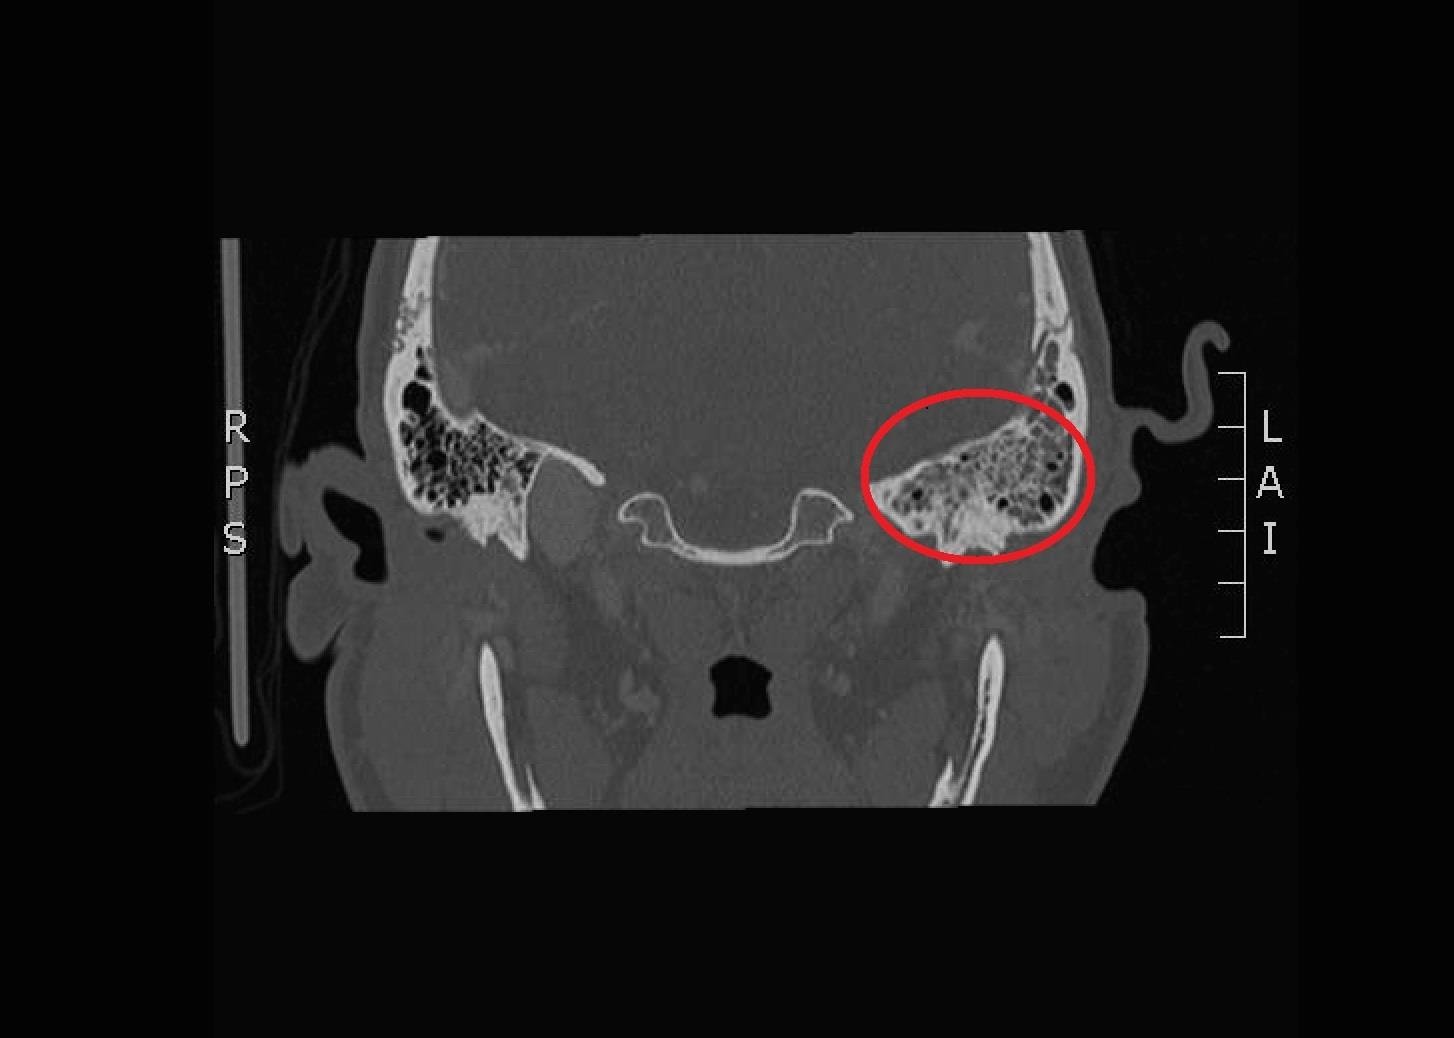

Significant findings:

The patient underwent computed tomography (CT) of the head which revealed opacification of the left middle ear (red arrow) and mastoid air cells (red circles). Additionally, there was thickening of the soft tissues of the external auditory canal (blue arrowhead), likely reflecting concurrent otitis externa.  Based on the imaging, he was admitted for findings consistent with acute otomastoiditis.